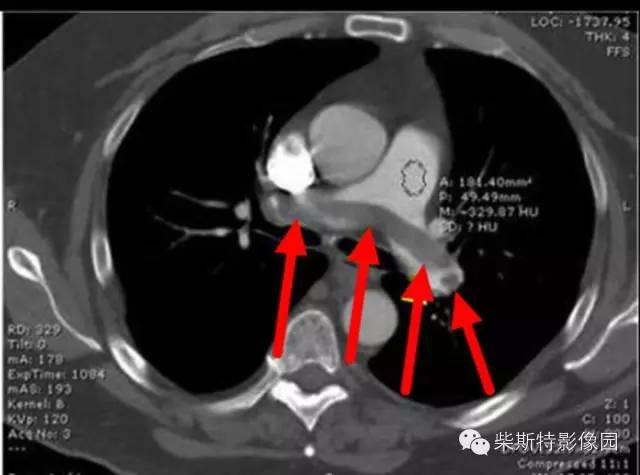

第二大名捕:肺动脉CTA

红色箭头所指处即栓塞导致的充盈缺损,从横断位、冠状位、矢状位三个层面观察,造影剂为高密度白色,而栓子的存在导致造影剂无法充填,从而表现为黑色的低密度影。俗话说的好:长江后浪推前浪!肺动脉CTA的本领已经基本超越其“大哥”肺动脉造影!还可以估测房室大小!